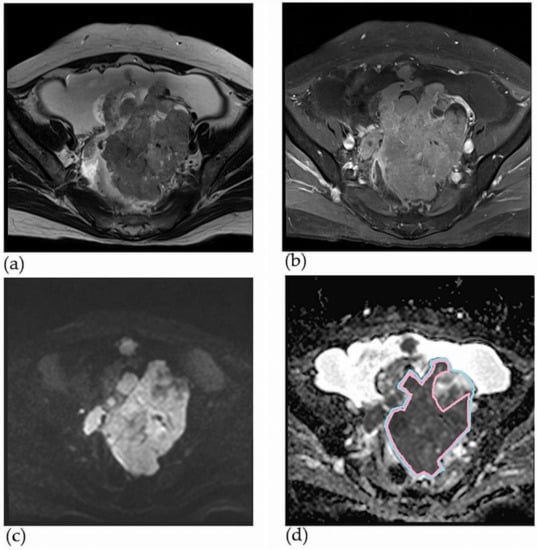

2.2. MRI Protocol and Interpretation